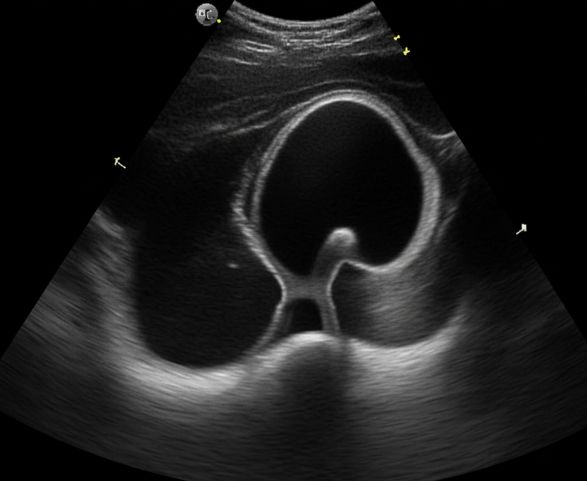

Diagnosis of UPJ Obstruction

🔹 Ultrasound – First-line imaging to detect kidney swelling (hydronephrosis) and assess urine buildup.